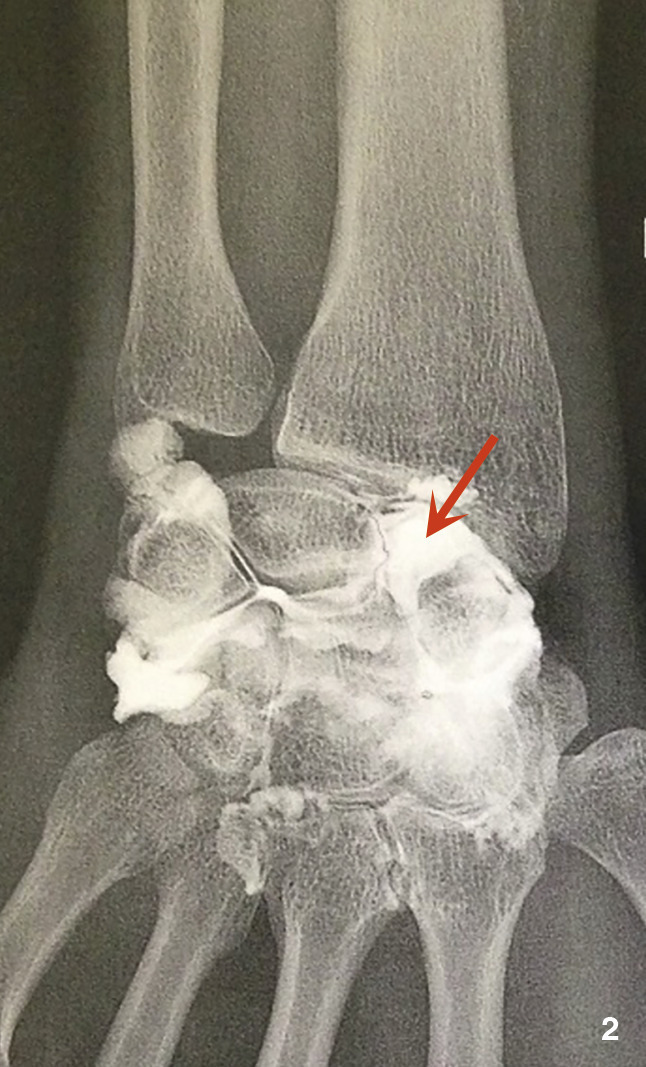

Un gendarme de 31 ans consulte pour des douleurs du poignet droit de plus en plus invalidantes. Deux mois auparavant : traumatisme en hyperextension du poignet (chute de sa hauteur) sans signe de gravité, pas de fracture sur la radio (fig. 1).

Une nouvelle série de clichés retrouve un diastasis scapholunaire.